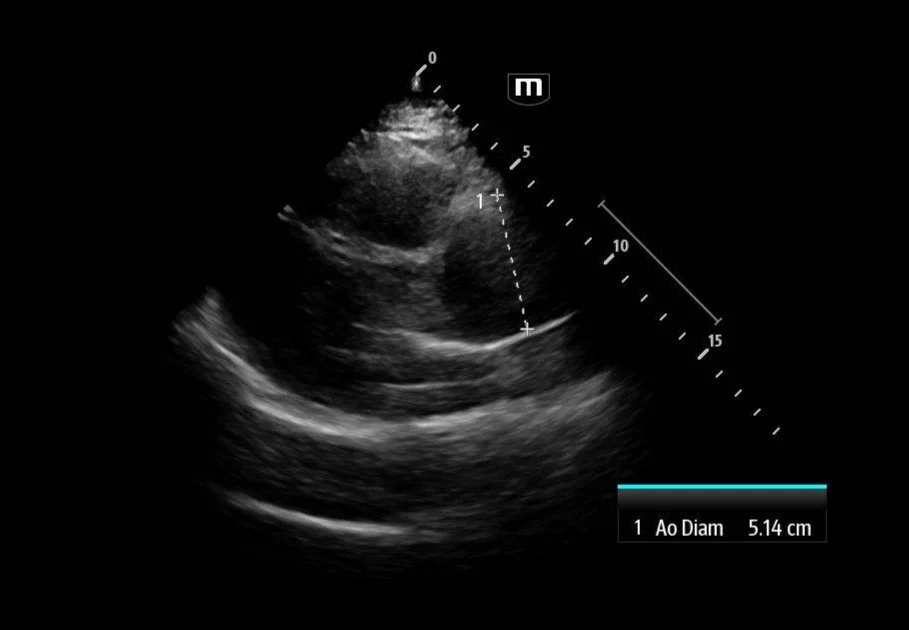

Image 1 & 2: Parasternal long axis

Interpretation: Parasternal long-axis view demonstrating marked dilation of the aortic root, measuring approximately 5.1 cm, concerning for proximal aortic pathology. Preserved EF and no effusions noted.

Teaching point:

• Normal aortic root diameter: < 3.7–4.0 cm

• A diameter >4 cm should raise concern for aneurysm or dissection